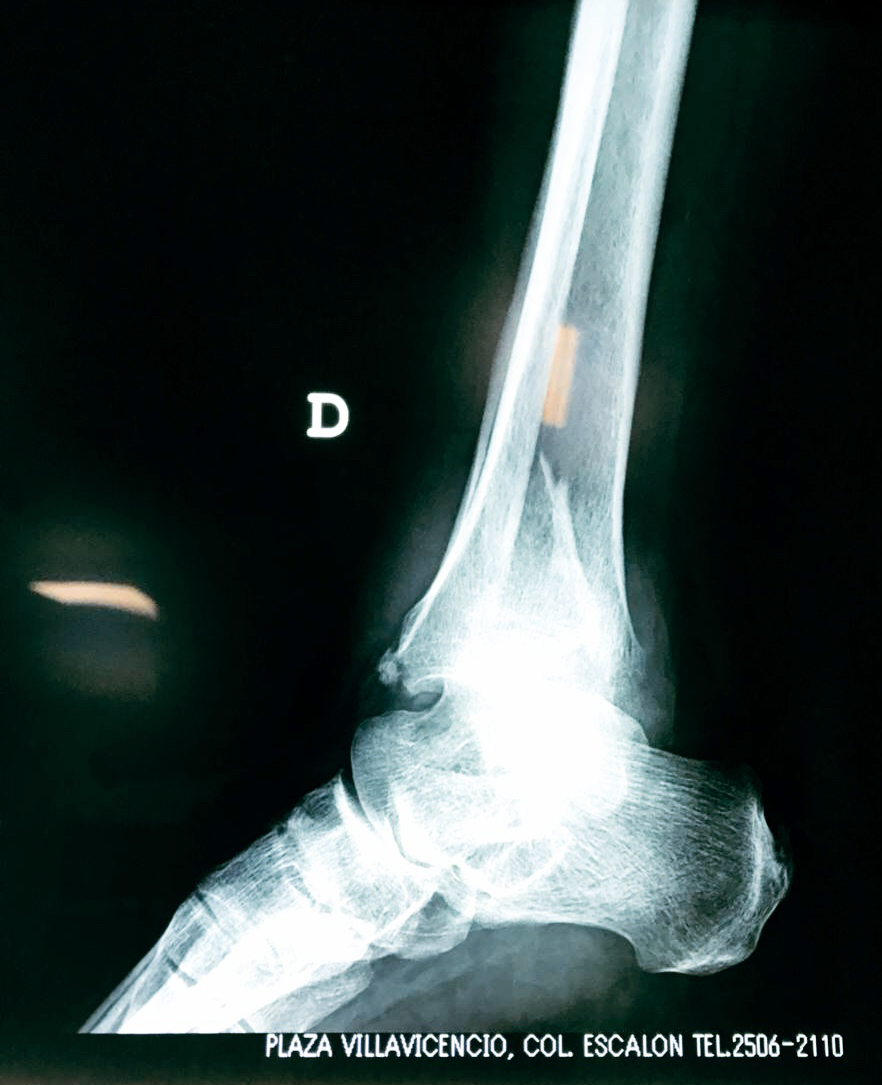

Una fractura de tobillo es la rotura de uno o más de los huesos del tobillo. Estas fracturas pueden ser:

- Parciales (el hueso está sólo parcialmente fisurado, no del todo).

- Completas (el hueso está perforado y está en 2 partes).

- Producirse en uno o ambos lados del tobillo.

- Los extremos de los huesos están desalineados entre sí (desplazados).

- La fractura se extiende hasta la articulación del tobillo (fractura intra-articular).